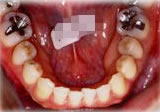

初診時年齢31歳7ヶ月。下顎側方偏位による咬合不全を主訴に来院。

顎変形と診断し、外科的処置を併用して治療。

下顎 下顎 下顎